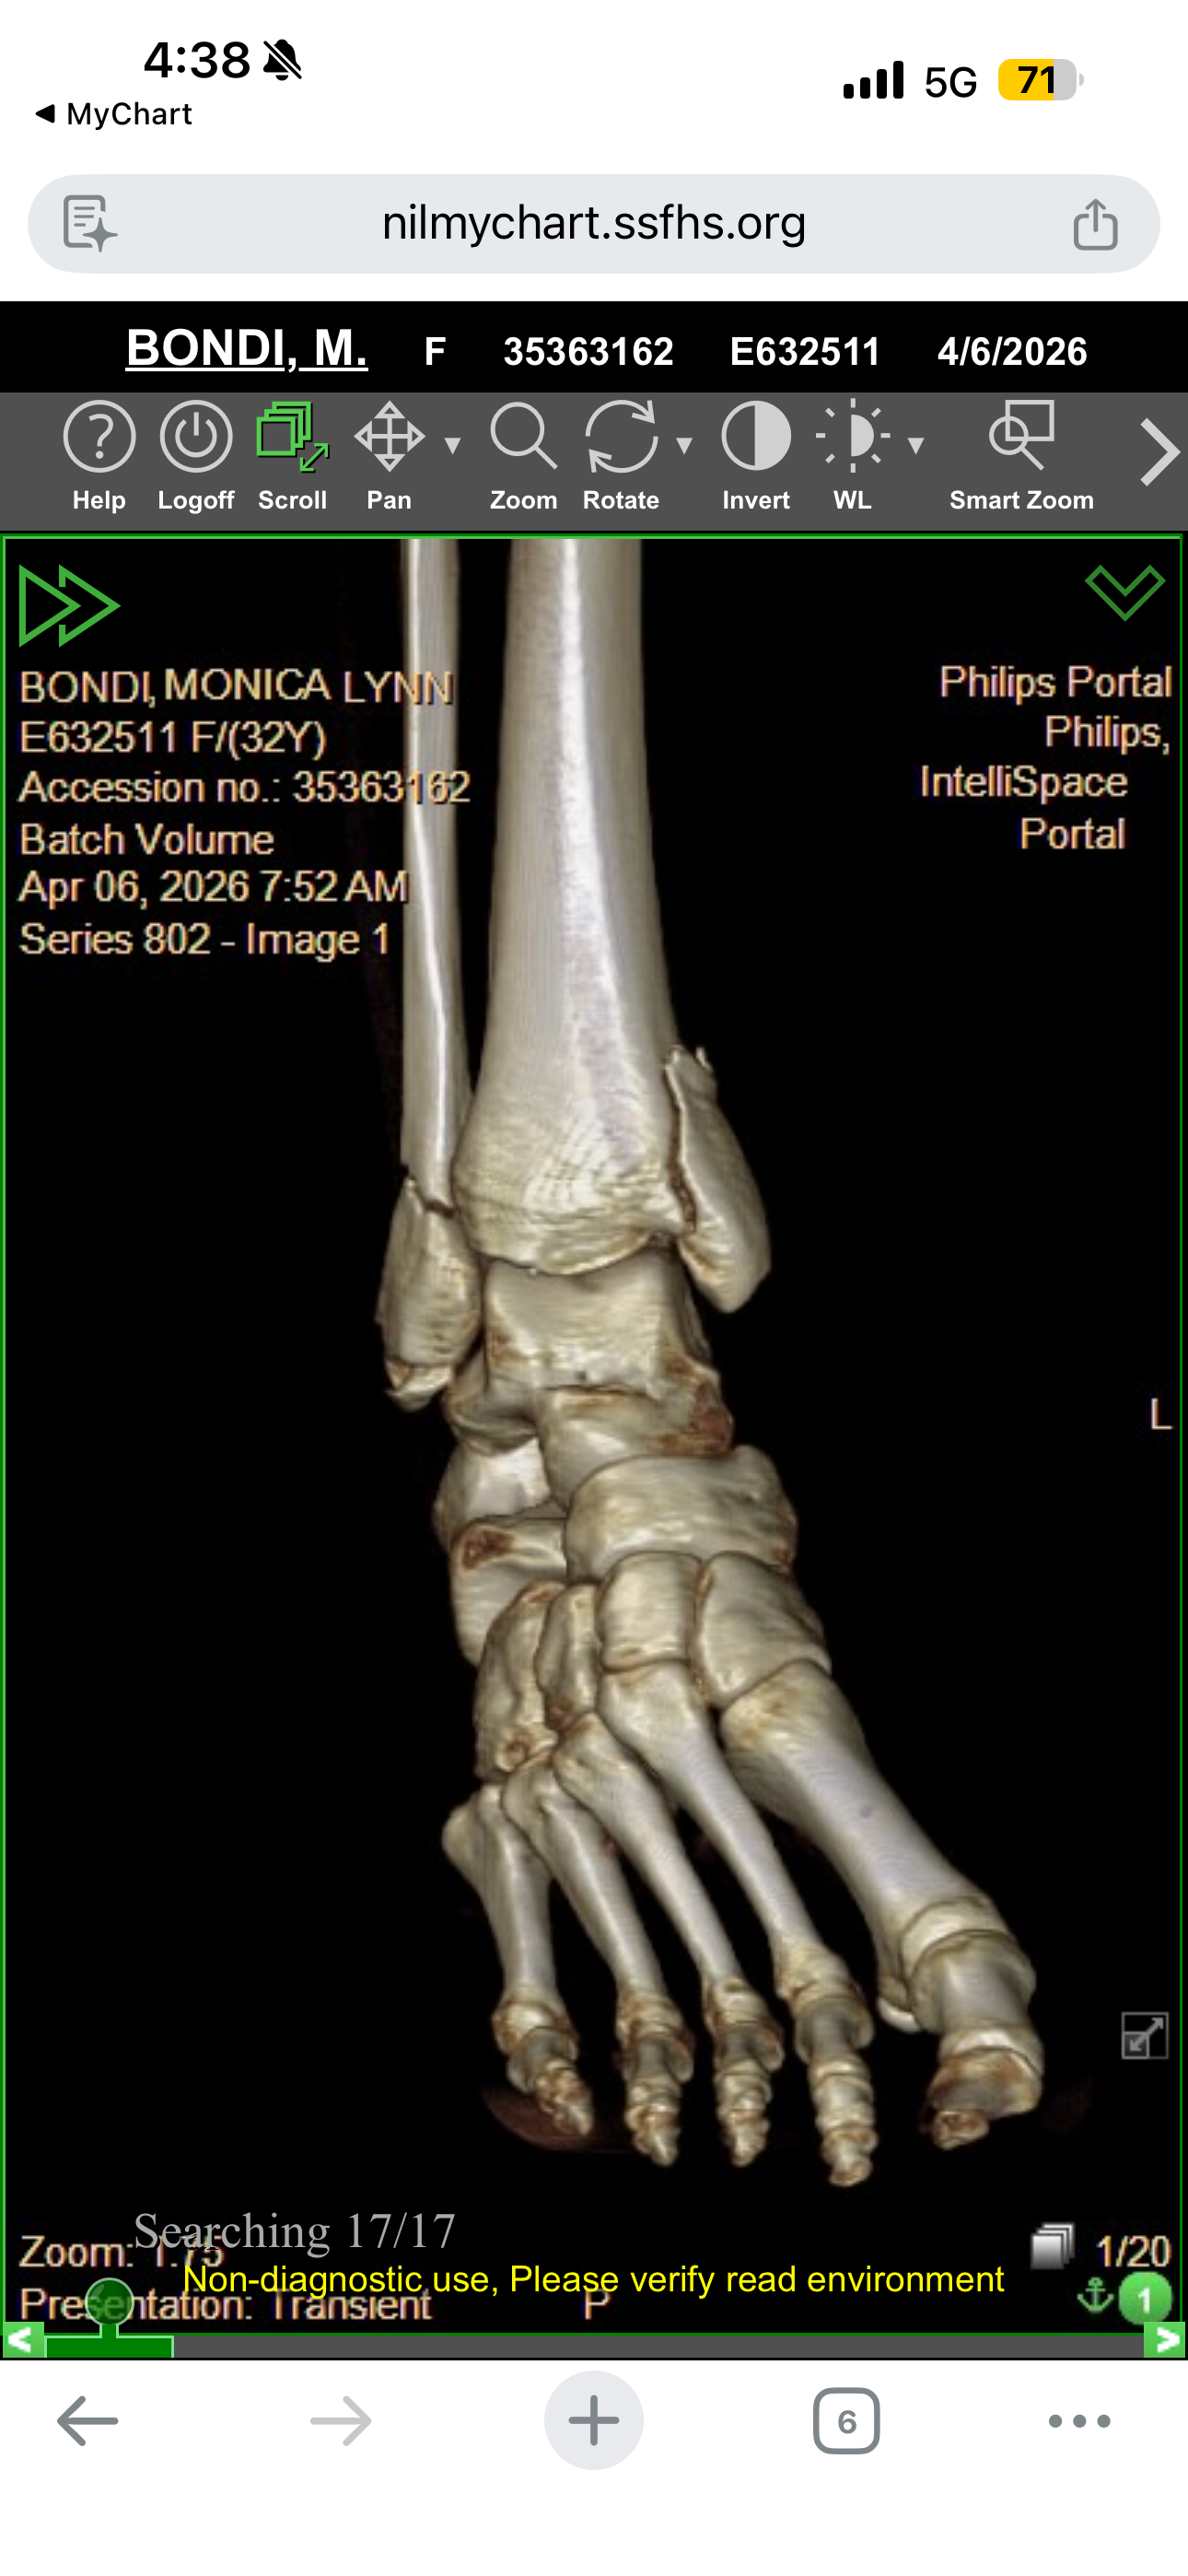

My name is Monica, and I'm a single mom of three wonderful kids. Recently, I experienced a life-changing accident when I jumped off my horse and broke every bone in my ankle. The injury was so severe that I needed surgery, which resulted in 13 screws and 2 plates being put into my ankle. The recovery process is long and challenging, and it's turned my world upside down.